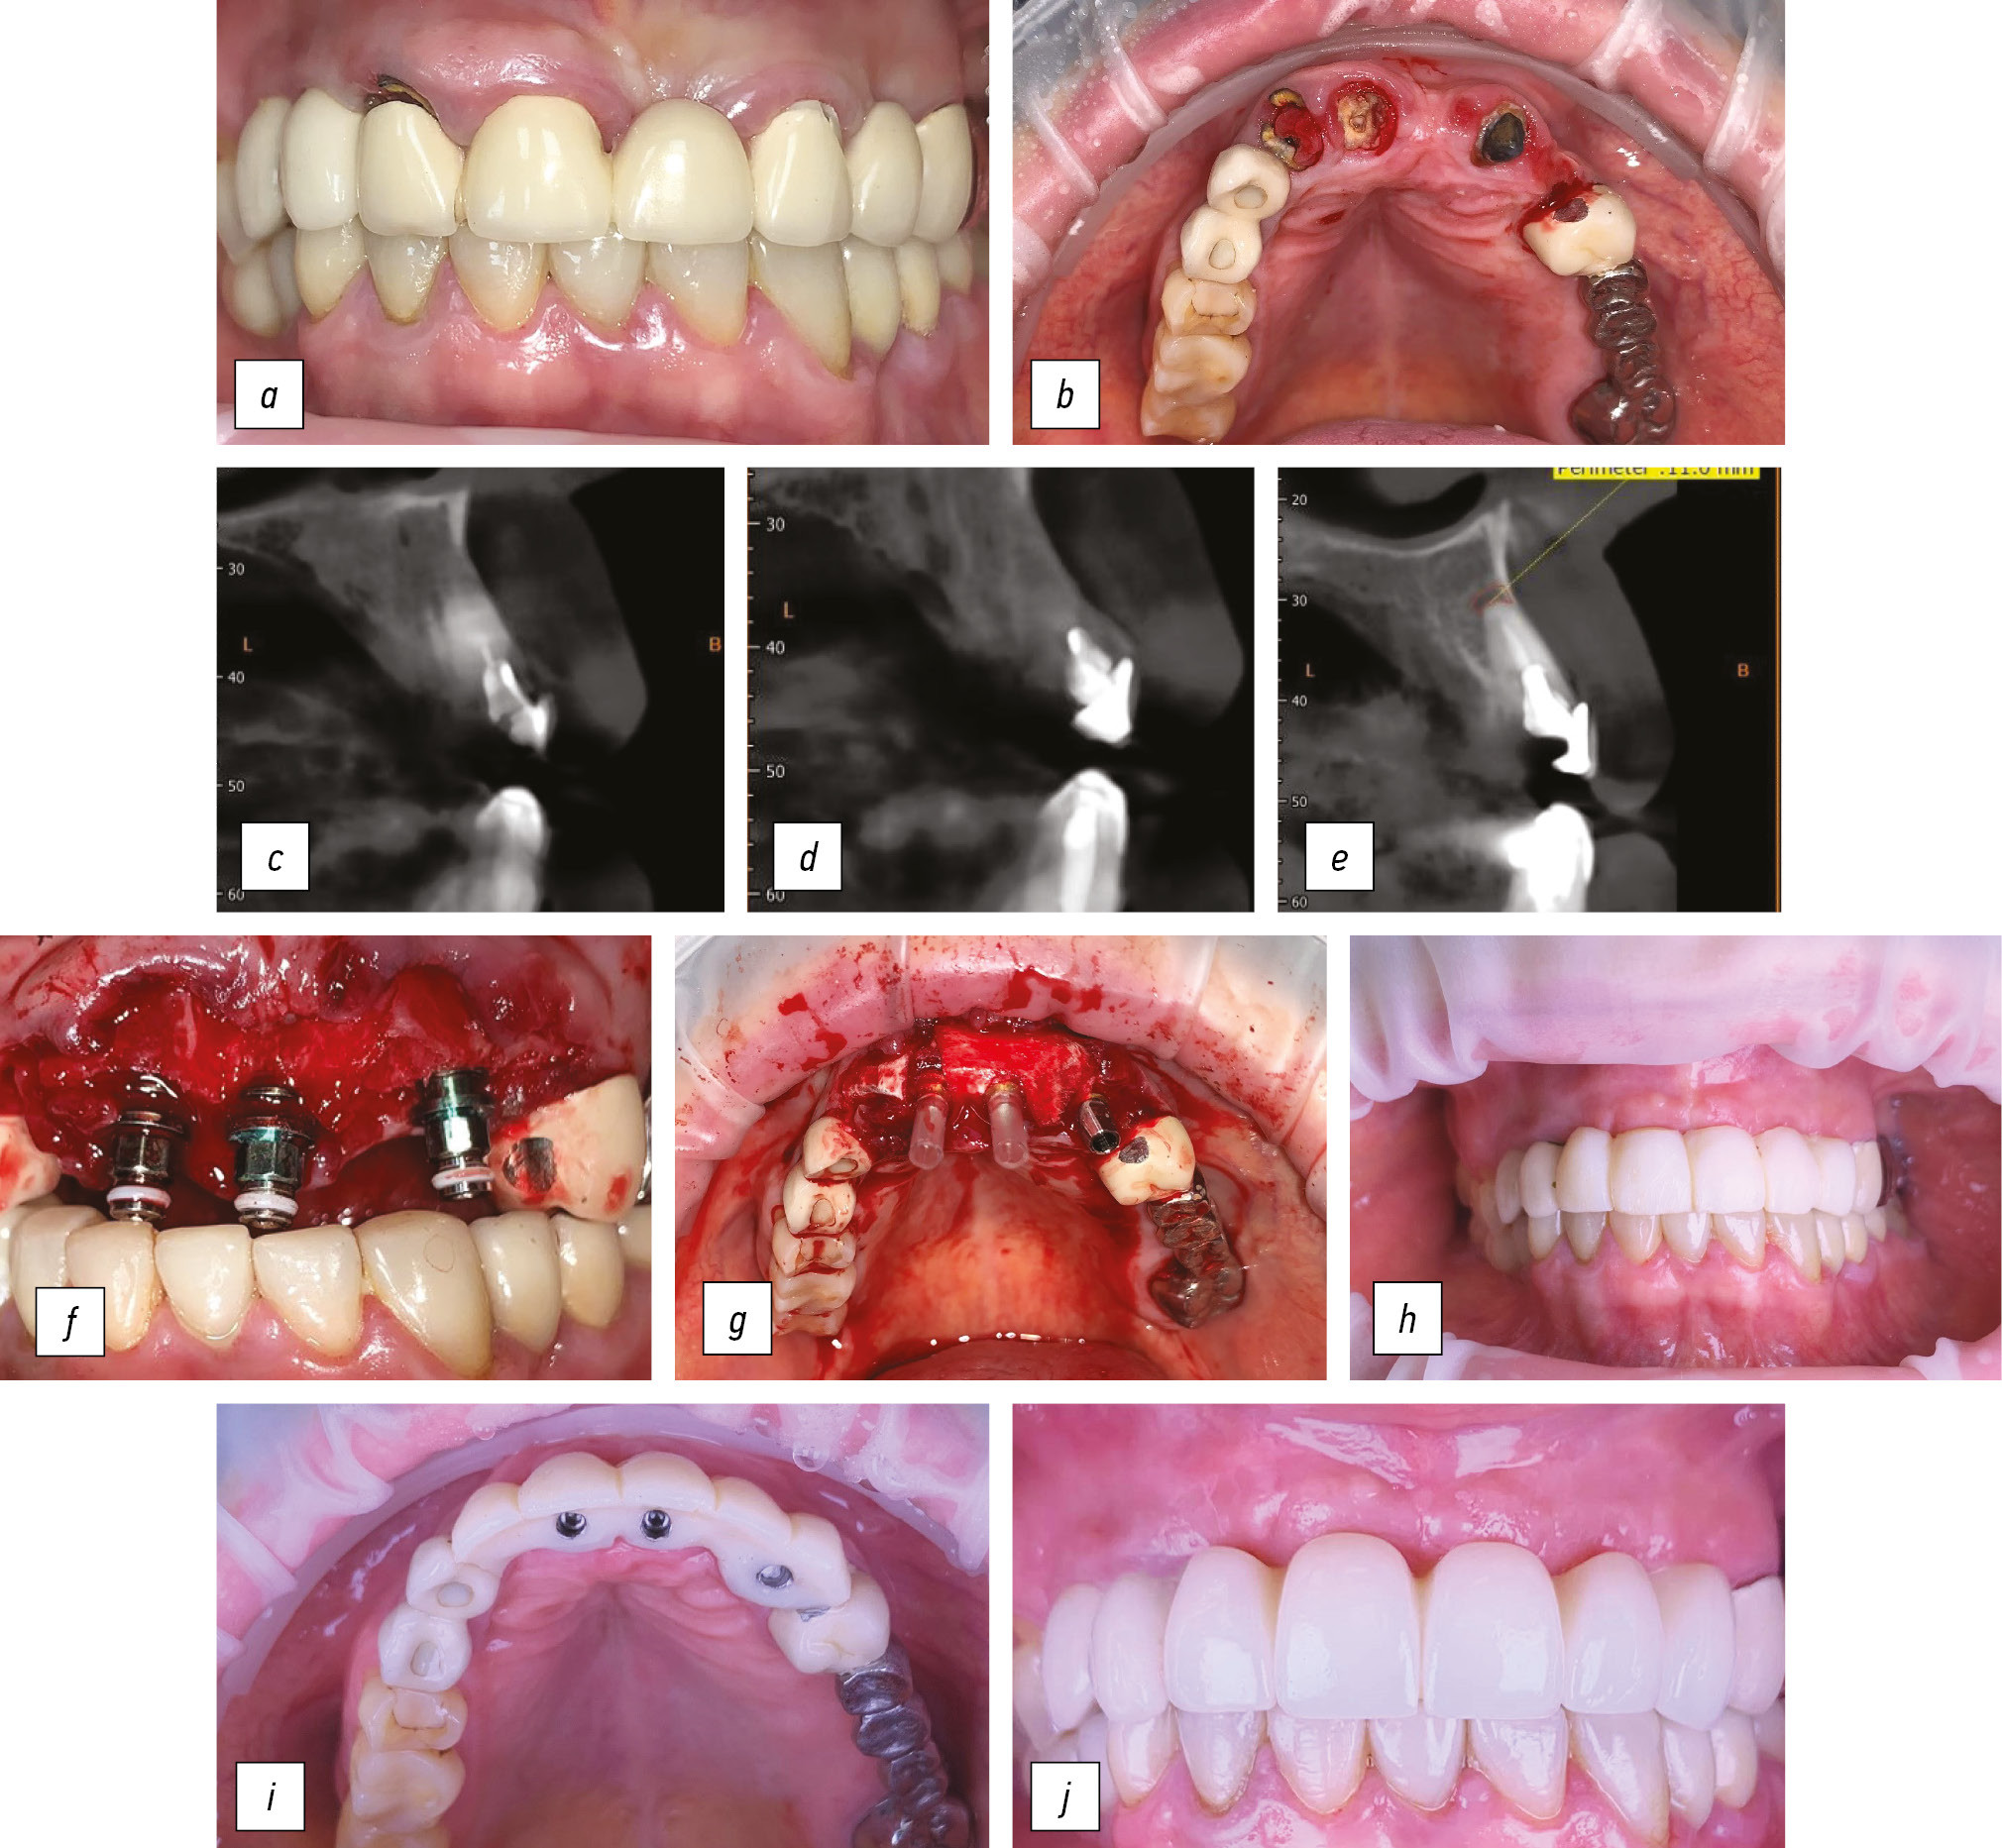

Рис. 5. Этапы стоматологической реабилитации пациентки Ж., 56 лет: а, b — исходная клиническая картина; c, d, e — срезы компьютерной томограммы фронтальной группы зубов на верхней челюсти; f, g — этапы хирургического лечения; h, i — установка временной ортопедической конструкции с немедленной нагрузкой; j — фиксация постоянных коронок из диоксида циркония.

Fig. 5. Stages of dental rehabilitation of patient J., 56-years-old: a, b — initial clinical picture; c, d, e — sections of a computed tomogram of the frontal group of teeth on the upper jaw; f, g — stages of surgical treatment; h, i — installation of a temporary orthopedic structure with immediate loading; j — fixation of permanent crowns made of zirconium dioxide.

Пациентка Ж., 56 лет, обратилась с жалобами на дискомфорт и периодически возникающие боли в области фронтальных зубов верхней челюсти (рис. 5). На аксиальных срезах компьютерной томограммы фронтальной группы зубов определяются комбинированные эндодонто-пародонтальные поражения с разрушением твёрдых тканей. Одномоментно с удалением зубов 1.2, 1.1, 2.2 выполнена установка дентальных имплантатов Synthes Pro в область зубов 1.1, 2.1, 2.2 с фиксацией мультиюнит-абатментов. Осуществлена направленная костная регенерация по ширине с заполнением всех образовавшихся после удаления дефектов костно-пластическим материалом с целью профилактики постэкстракционной атрофии. Фиксация временных коронок была проведена в тот же день. Через 3 мес после стабилизации тканей в периимплантной зоне временные ортопедические конструкции заменены на постоянные из диоксида циркония.